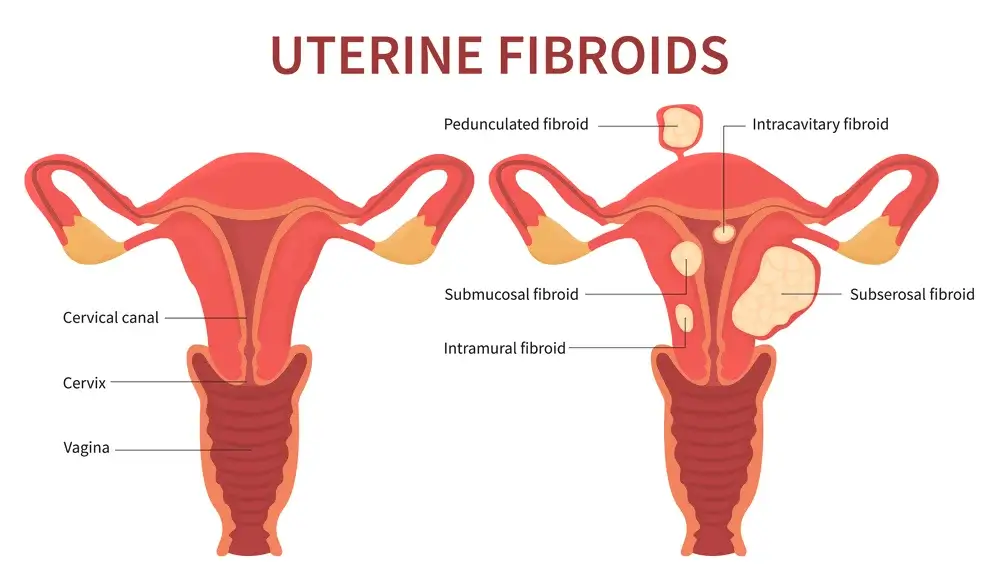

Uterine Fibroids and Back Pain:

Uterine Fibroids are a common condition that affects many women’s health. The medical term for them is leiomyomas, and they can happen in any woman who has a uterus. Uterine Fibroids are non-cancerous tumors that grow on the walls of the uterus, and they can vary in size from very small to very large. Acupuncture can also be beneficial for helping reduce symptoms of uterine fibroids and back pain.It is common, and can cause pain, heavy periods and even infertility. There are several treatments available for uterine fibroids, but some people prefer to use natural methods.